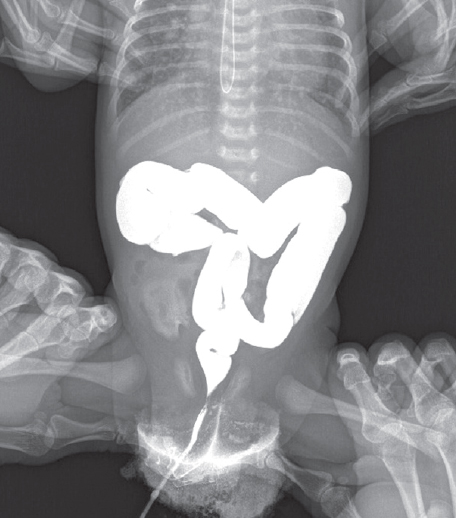

Из таблиц 1 и 2 следует, что наиболее часто встречающимися рентгенологическими признаками являлись левосторонне расположенная толстая кишка (30 %) и высокое стояние слепой кишки (39 %) (рис. 1).

Рис. 1. Левостороннее расположение толстой кишки (слева), высокое расположение слепой кишки (справа) у новорожденных, ирригография

Fig. 1. Left-sided location of the colon (left), high location of the cecum (right) in neonates, irrigography

В восьми случаях (18 %) левостороннее расположение толстой кишки сочеталось с атипичным расположением слепой кишки (высокое стояние или высокое и срединное положение) (рис. 2).

Рис. 2. Высокое и срединное положение слепой кишки у новорожденного, ирригография

Fig. 2. High and medial position of the cecum in a newborn, irrigography